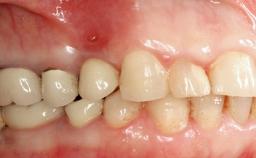

A 77-year-old male patient was referred for the management of frequent and repeated acrylic fracture of his existing mandibular fixed full-arch implant-supported metal/acrylic prosthesis. He also complained about softtissue soreness and the lack of retention and stability of his maxillary removable partial metal/acrylic prosthesis. Both prostheses had been delivered two years previously as part of his full-mouth rehabilitation (caries, tooth wear, tooth fracture). His medical history revealed high blood pressure, controlled with the use of antihypertensive medication.